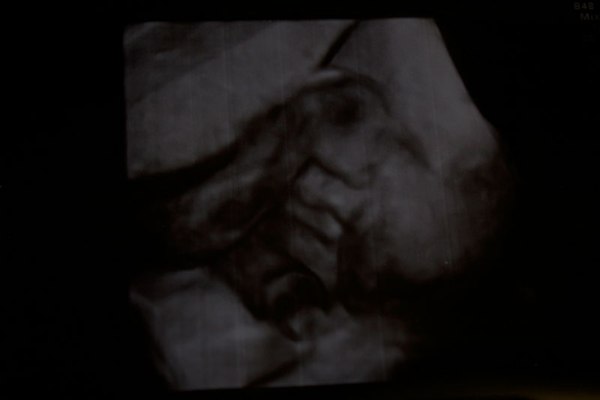

Scanbilde i uke 31+4:)

Jeg kan jo ikke dy mig, men må vise fram min lille gringo som vi fik lov til at kikke ind til igjen i dag

Takk, jo, det er vilt fett, selv om han ser litt alienagtig ud

Tusen takk piger Og det er faktisk ikke en 3d scanning, men man kan tydelig se ansigtstrækkene likevel

Det var dog et fantastisk skanningsbillede, og så er det ikke engang 3D...